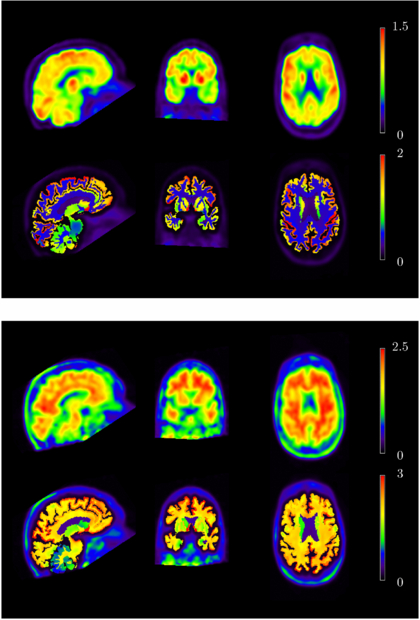

2.7. Example

This example is for illustration purposes only. A phantom simulation study was performed in order to compare some of the PVC methods described above. A 2D synthetic phantom was used, consisting of a hot annulus and a cold centre. This could represent a brain study with GM (annulus) and WM (centre), or a cardiac study with myocardium (annulus) and ventricle (centre), or an oncological study with viable tumour (annulus) and necrosis (centre). The central region was uniform with a relative activity concentration value of 1, and the annular region was divided into various sections. On the left hand side, the main part of the annulus had a value of 4, except for a 30° cold-spot with a value of 2. The right hand side was divided into three 60° segments with values of 3, 4 and 8, respectively. Normally distributed random noise was added to the phantom which was then convolved with a PSF with a FWHM corresponding to 80% of the width of the annulus. PVC was performed as described above, using the MGM, GTM and RBV methods.

Figure 5 shows the true distribution in the phantom, the regional masks (or templates) used in the different methods, as well as the uncorrected and PV corrected images, using MGM and RBV. The MGM regional mask consisted only of the background (centre) and target (annulus) regions, while the RBV and GTM mask contained all the original regions except for the left-hand side cold-spot, which was treated as unknown. The difference between the masks is due to the fact that, although multiple background regions can be used with MGM, there can only be one target region in which the correction is applied. On the other hand, RBV and GTM can use any number of regions, and the correction is applied to all regions.

Figure 5. Top row: original phantom and regional masks (templates) used for MGM and RBV. Bottom row: the uncorrected simulated image with added noise and resolution blurring, and results after PVC with MGM and RBV.

Download figure:

Standard imageIt is clear from the images that the contrast in the annulus as well as the sharpness of the boundaries increases after PVC with both MGM and RBV. The difference between the two methods is that, while MGM does not perform any correction within the annular target region, RBV does correct for cross talk between different regions within the annulus. Also, the RBV corrected image retains information about the distribution in the central region, whereas in the MGM corrected image this region is just represented by a constant value. The left-hand side cold-spot is clearly visible in both PV corrected images.

Figure 6 shows quantitative results, including the GTM results. Mean regional values were calculated for all the original phantom regions, and relative bias and the coefficient of variation (COV = SD/mean) values were obtained based on 30 noise realisations of the phantom. One conspicuous detail is the large bias obtained with GTM in ROI 3 (the unknown cold-spot). The voxel-based methods have a much lower bias, since they preserve the original image distribution within the regions. Even in ROI 2, MGM and RBV give a lower bias than GTM (for the same reason). In ROIs 4–6 all PVC methods have quite low bias, although this time MGM has a larger bias than GTM and RBV. This is because it does not correct for the cross-talk between different annular regions. The variability, given by the COV, is similar for all methods.

Figure 6. ROI analysis of phantom simulation from figure 5; the graph shows bias in different regions for the uncorrected image (plus-signs, solid line), and images corrected with the MGM (asterisks, dotted line), RBV (diamonds, dashed line), and GTM (squares, dot-dashed line) methods. The left inset shows the ROI number corresponding to each region in the phantom. The true relative activity concentrations for regions 0–6 were as follows: 0:0, 1:1, 2:4, 3:2, 4:3, 5:4, 6:8. The graph shows the bias relative to the true values for all regions except region 0, for which the absolute bias is presented. The error-bars represent regional COV values.

Download figure: